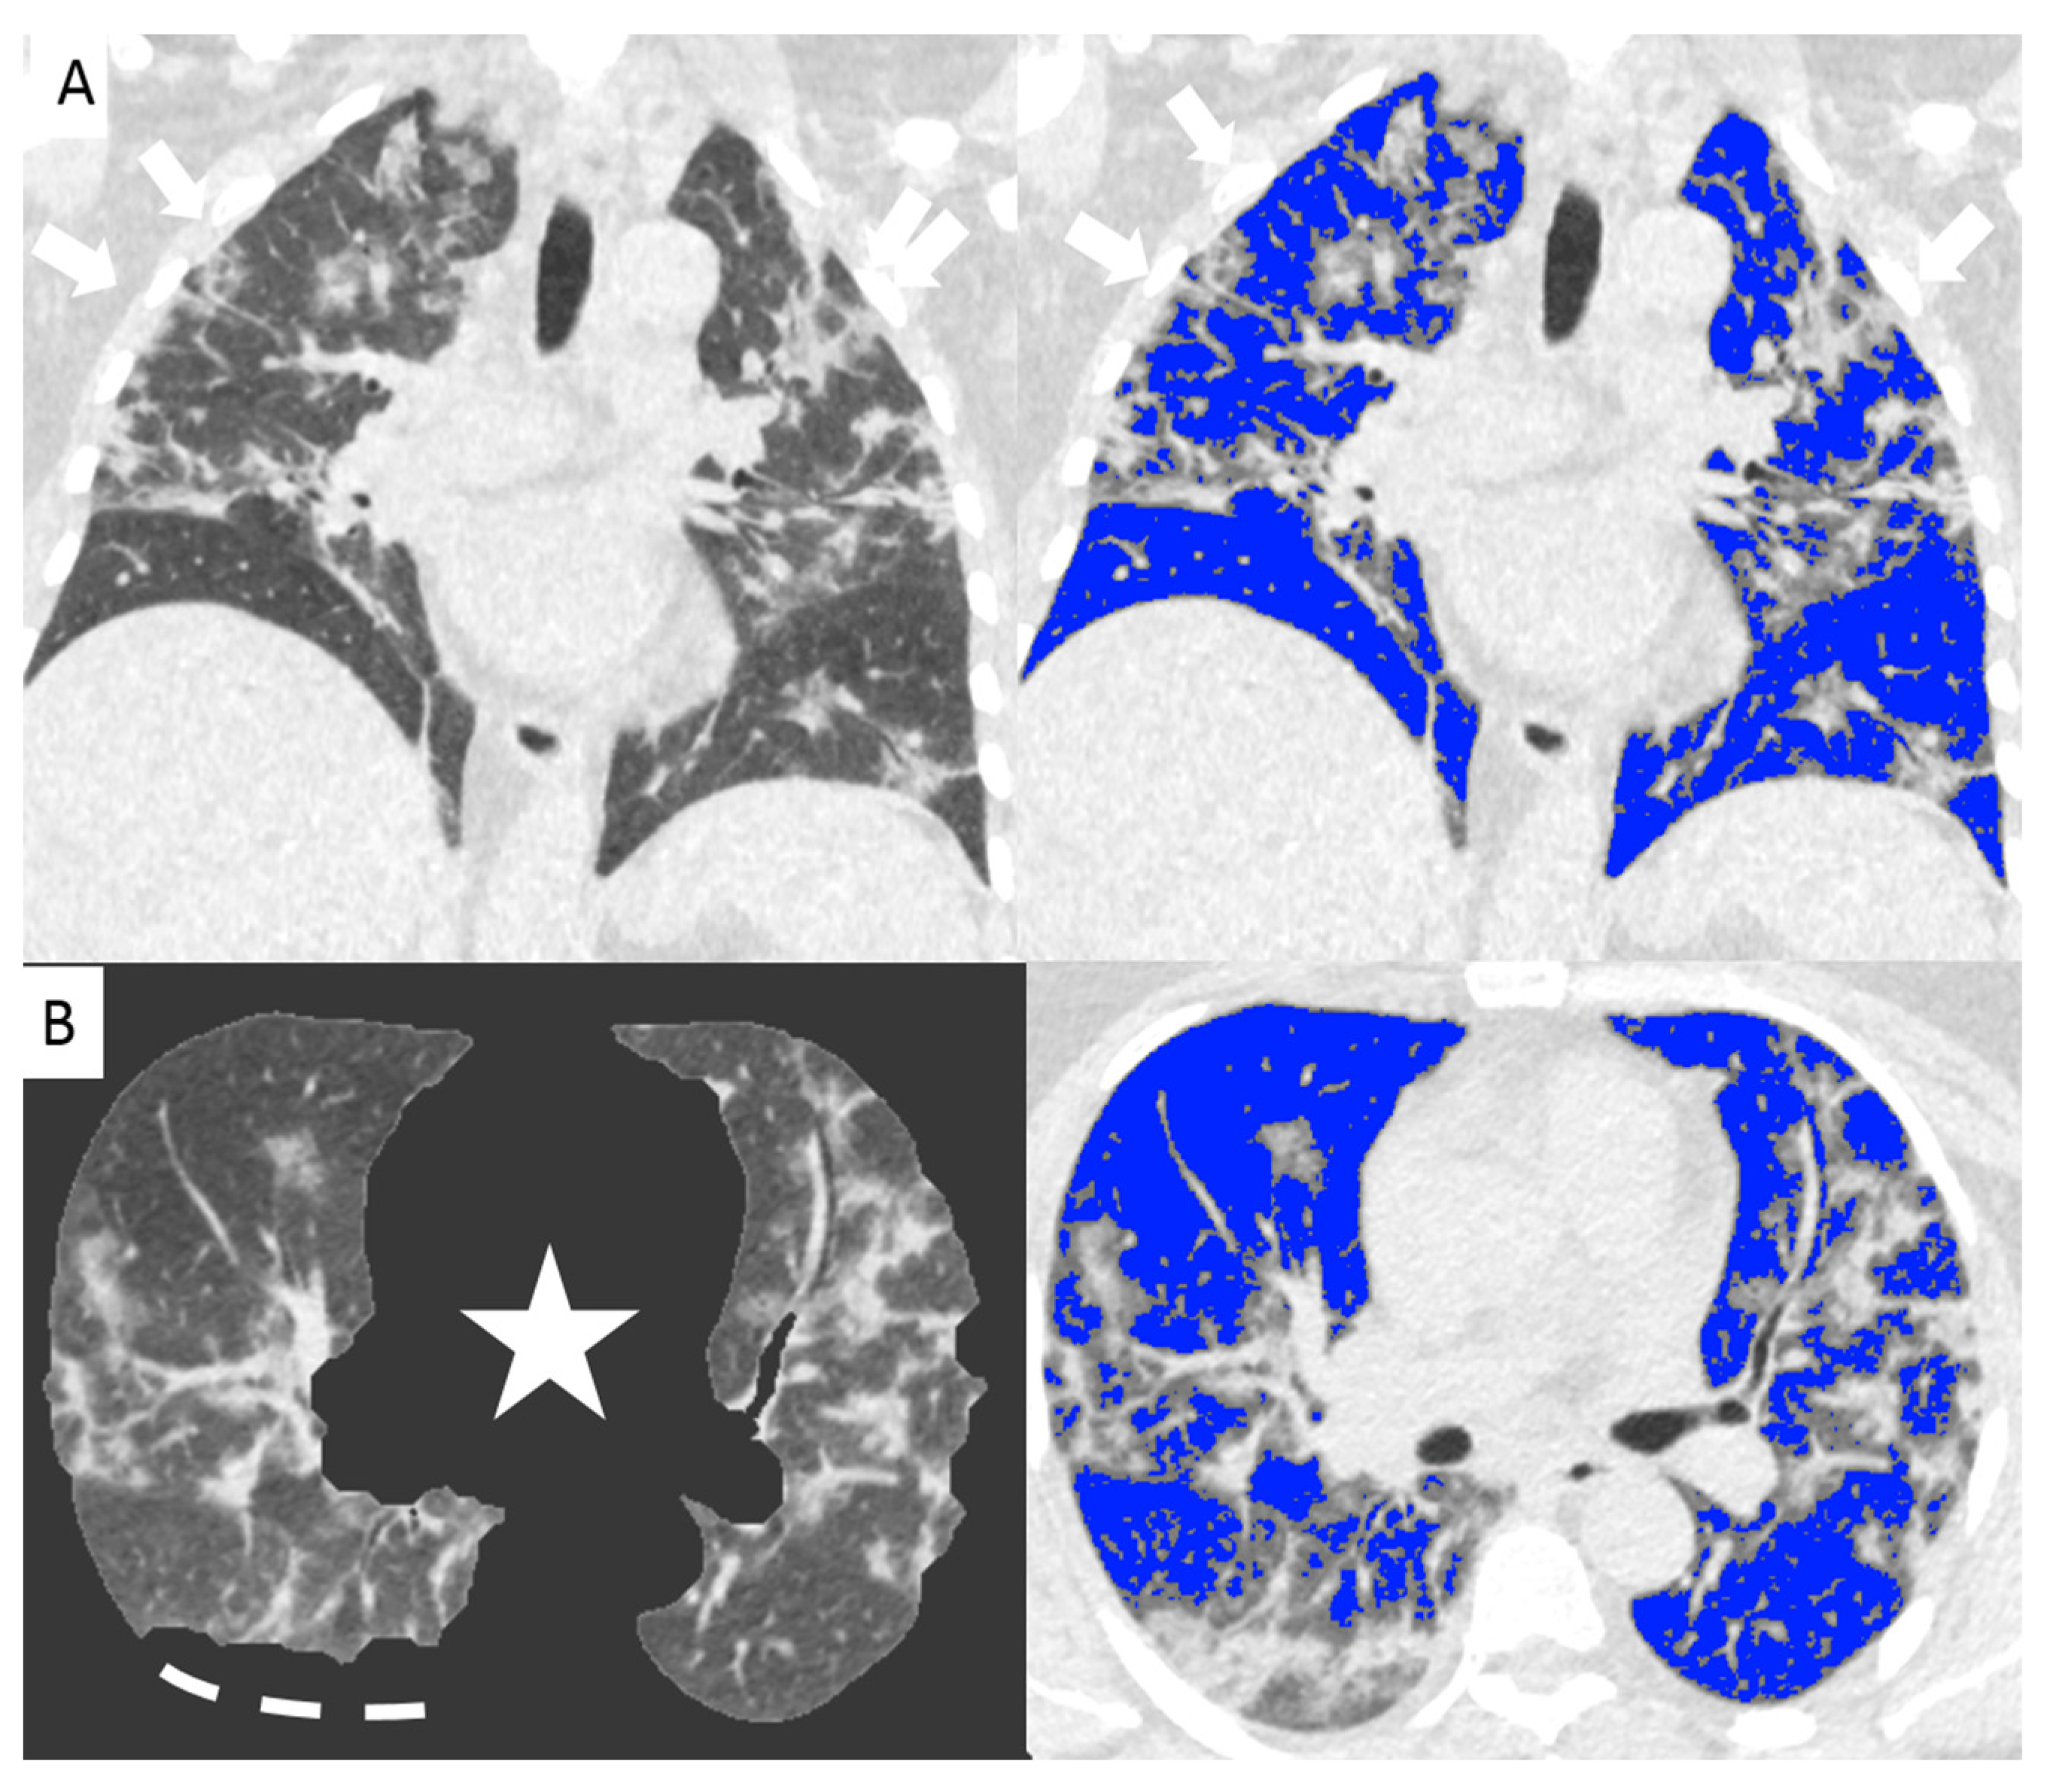

Since the beginning of the Covid-19 outbreak certain diagnosis of the disease was complicated by the multiplicity of symptoms and imaging features and due to the variability in the severity of disease at the time of presentation [1]. Chest CT has demonstrated an important role in predicting patients’ outcome because of the correlations between CT features and the severity of the disease [7,13]. In our study we demonstrated the correlation between the lung volume affected by the COVID-19 pneumonia and clinical outcome with a direct relationship between the infected lung percentage and the need for ventilation or subsequent death. Figure 2 and Figure 3 show lung volume analysis with dedicated software in comparison with standard CT images.

Figure 2.

Non-enhanced coronal reconstructions of Chest CT (A), (upper panel) showing bilateral ground glass opacities with random distribution and consolidations in the upper and lower lobes (arrows). Lower panel show axial CT reconstructions of the same patient with automatic software segmentation (B) excluding all “non-lung” structures, (star) and not evaluable parenchyma due to pleural effusion (segmented line). Images on the right show software evaluation of the well aerated lung (blue) and the infected parenchyma (grey zone, arrows) discriminated by specific threshold. The whole infected volume assessed by software was 47% of the entire lung volume. The patient underwent invasive ventilation.